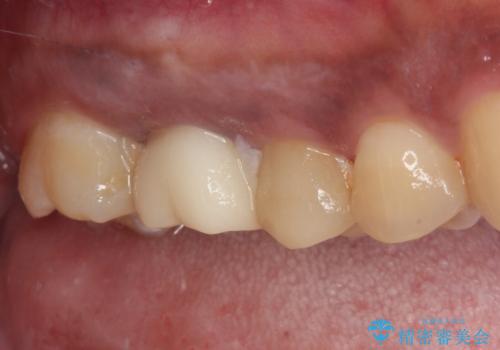

不快感の強い奥歯 オールセラミッククラウンでのむし歯治療

- とにかく奥歯に不快感を感じるとのことで来院された患者様です。

神経近くにまで及んでいる大きなむし歯や、歯肉の中深く、骨の近くにまでむし歯が進行している歯など、問題の多い状態でした。

神経を温存するための処置や、歯肉深くにまで及んだむし歯を改善するための歯周外科処置などを行っていき、オールセラミッククラウンにて補綴治療を行うこととしました。

術前の診断では神経が温存できるか否か、際どい状況でしたが、治療開始前の海外への帰省の際に自発痛(何もしなくてもズキズキ痛む)の症状が出てしまい、根管治療が必要となってしまいました。